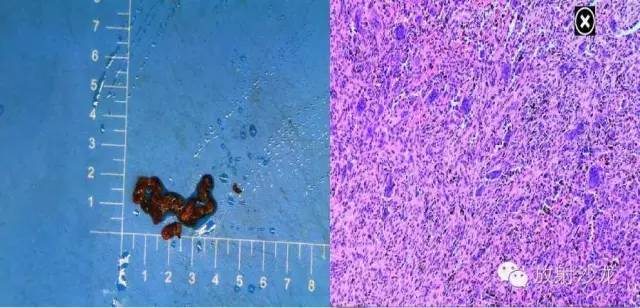

【术后病理】

【病理】

影像学表现:送检灰白灰褐碎小组织多块,总体积3cm×2cm×0.5cm。

影像学诊断:(鼻腭)送检纤维性肉芽组织伴陈旧性出血,部分区域可见多量多核巨细胞,及少量反应性骨组织,结合临床部位,考虑巨细胞修复性肉芽肿。